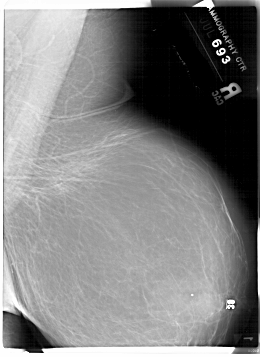

A_1882_1.LEFT_CC

LEFT_CC LINES 6601 PIXELS_PER_LINE 4816 BITS_PER_PIXEL 12 RESOLUTION 43.5 OVERLAY